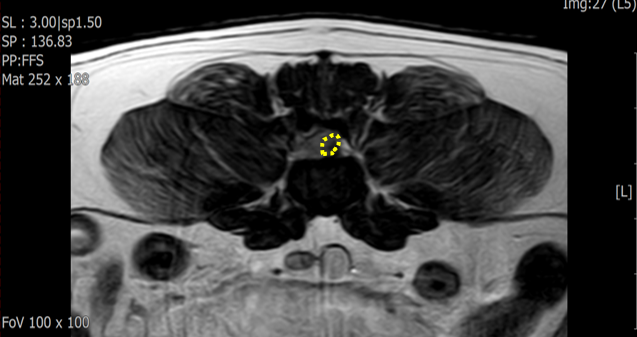

첫번째 환자는 9살령 중성화 수컷이었고, 5.5kg으로 비교적 작은 체형의 개였습니다. 증상은 전날 갑작스러운 후지마비 증상을 보여 내원하였고, 내원시에 Grade 5로 deep pain도 소실된 상태였습니다.

Mri 검사상 요추 4/5번 좌측으로 디스크 탈출이 확인되었습니다.(사진2)

증상의 정도가 심하여 충분한 감압을 위해 수술은 Hemilaminectomy 를 계획하여 실시하였습니다.(사진3,4)